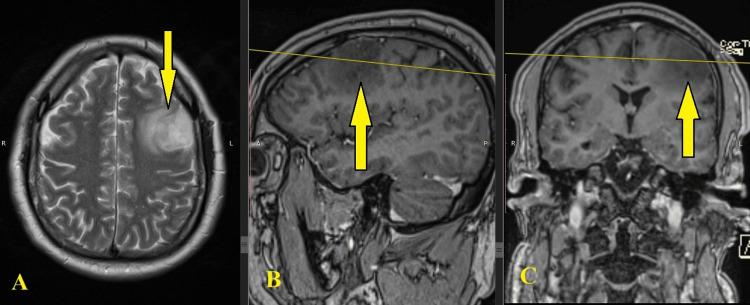

Awake craniotomy is a surgical procedure that has been gaining significance over the past decades. Neuronavigation is an intraoperative technology that locates tumors and monitors the brain cortex during awake craniotomy. The presence of cerebral low-grade gliomas in the frontal lobe creates a risk of affecting vital centers of the brain cortex during surgery. We present a clinical case of a 42-year-old male patient who entered the neurosurgery clinic with a clinical manifestation of headache for two months. MRI showed evidence of the recurrence of a left frontal glioma. Differential diagnoses of frontal gliomas include metastases, abscesses, and cysts. The pathophysiologic background of the disease is the mutation of neuroglial cells, which leads to an abnormal and uncontrollable proliferation. Under sleep-awake anesthesia, operative treatment was performed through left frontal awake craniotomy under neuronavigation. As a result, a total excision was achieved. Motor functions of the right limbs and speech have been preserved. The patient was mobilized on the day after the intervention. Surgery-related complications were not observed. The patient had relief from the symptoms and was discharged on the fifth day. Awake craniotomy combined with neuronavigation was the most efficient and the least harmful method for the excision of the tumor. For low-grade gliomas localized in the frontal area of the encephalon, awake craniotomy is the only secure option for surgery.

清醒开颅手术是一种在过去几十年中越来越重要的外科手术。神经导航是一种术中技术,可在清醒开颅手术期间定位肿瘤并监测脑皮质。额叶存在脑低度胶质瘤会在手术期间产生影响脑皮质重要中枢的风险。我们介绍一例42岁男性患者的临床病例,该患者因头痛两个月的临床表现进入神经外科门诊。磁共振成像显示左侧额叶胶质瘤复发的证据。额叶胶质瘤的鉴别诊断包括转移瘤、脓肿和囊肿。该疾病的病理生理背景是神经胶质细胞的突变,这导致异常且无法控制的增殖。在睡眠-清醒麻醉下,通过神经导航下左侧额叶清醒开颅进行手术治疗。结果,实现了肿瘤全切。右肢运动功能和言语功能得以保留。患者在干预后第二天即可活动。未观察到手术相关并发症。患者症状缓解,并于第五天出院。清醒开颅手术联合神经导航是切除肿瘤最有效且危害最小的方法。对于位于脑额叶区域的低度胶质瘤,清醒开颅手术是唯一安全的手术选择。